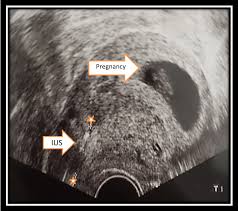

In that case, the device may disrupt a fertilized egg, again, in a small number of cases. A positive test is definitely one of the biggest signs of pregnancy with an iud. You might be pregnant if your iud has slipped or moved out of place…or, if you are pregnant, your iud may be trying to dislodge the embryo from the uterine wall…this would cause spotting. You also have a higher. If you have an ectopic pregnancy, that means the egg has attached to the outside of the uterus and you will need additional medication or surgery to remove it. How we handle pregnancy with an iud in this image, an iud in the cervix is visible as a white line on the right side. See your doctor.getting pregnant while using an iud increases the risk of an ectopic pregnancy (in which the egg implants outside of the uterus). The best way to know if your iud is out of place is to check the strings regularly.